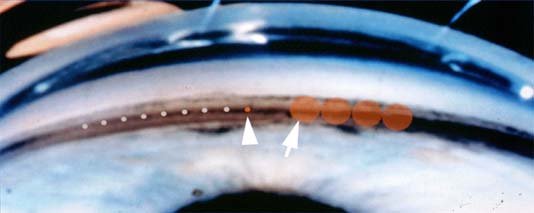

Argon laser는 laser burn의 크기가 50um이며,

섬유주의 여과부와 비여과부 사이를 aiming 해서 레이저 치료를 하게됩니다.

반면, SLT의 경우는 laser burn 의 크기가 400 um로 상당히 큽니다.

한번조사하게되면, 섬유주 전체를 모두 커버할수 있을 크기입니다.

레이저 응고반과 레이저 응고반사이가 서로겹치지는 않지만, 서로 연속하다는 느낌이 들도록,

180도에 50개 / 360도에 100개 정도가 되도록 레이저를 시행합니다.